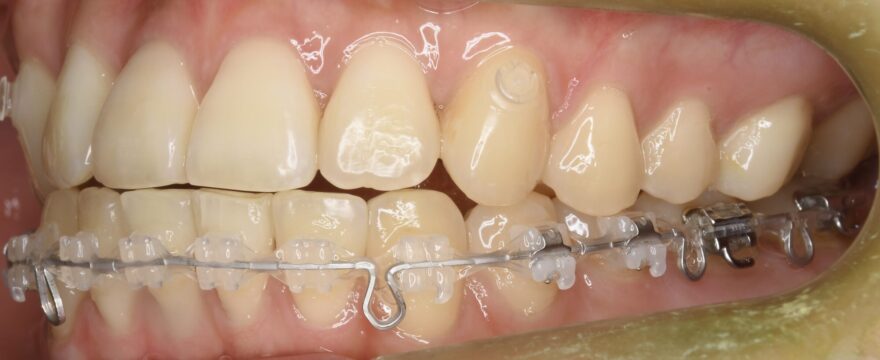

治療中の口腔内写真

上顎は裏側に矯正装置が付いています。

口蓋に2本の歯科矯正用アンカースクリューが埋め込まれ、裏側の矯正装置とゴムで繋がっていることがわかります。